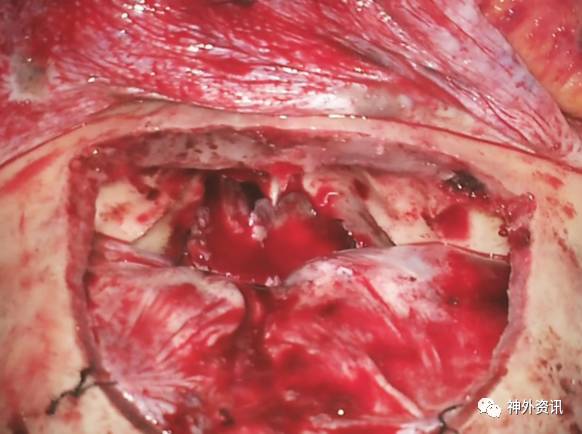

图11. 在肿瘤完全切除、采用颞肌筋膜瓣修复硬脑膜缺损使其完全闭合后,颅底可见一大的骨质缺损。本图上部显示的是完整的骨膜瓣。

图12. 如果术者希望通过双额入路抵达完全位于硬膜内的肿瘤,比如脑膜瘤,于平行骨缘方向切开硬脑膜(A和B)。上矢状窦前部用0号丝线间断结扎,然后离断。尽管矢状窦旁前部的桥静脉被认为是不重要的,但术者在牺牲它们的过程中仍要小心。吸引器头端清晰可见肿瘤组织(C)。缺损的硬脑膜采用一块颞肌筋膜瓣完全封闭,额窦利用骨膜瓣覆盖(D和E)。